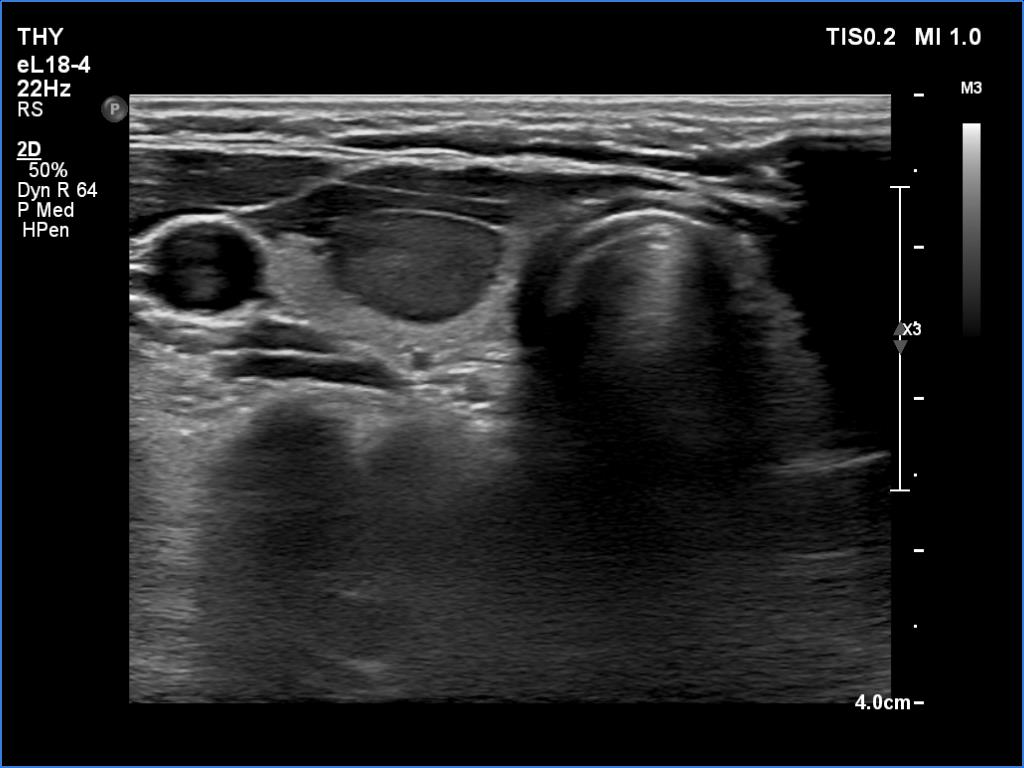

Ultrasonography. The thyroid was echonormal. There was a moderately hypoechoic nodule in the ventral part of the right lobe. This lesion has regular, sharp margins and presented signs of a possible extrathyroidal spread. The intranodular vascularity was increased. The left lobe had a tiny, minimally hypoechoic lesion. The largest diameter was 7 mm. The lesion had both echogenic lines and granules, a pattern corresponding either to connective tissue or back wall figure. The lesion had neither halo nor perinodular blood flow.

The nodule in the right lobe is remarkable because of the hypoechogenicity, the increased vascularity and because it shows sing of a possible extrathyroidal spread.